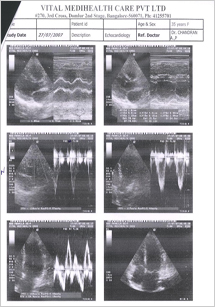

Echocardiography was done indicating a normal heart and patient is un symptomatic. Final Echocardiography was done and shown in FIG 4

FIG 4:- Echocardiography report of 4th JAN 2008